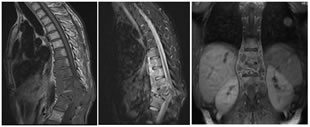

A; SAGITTAL T1W; B: SAGITTAL T2W; C: CORONAL T1 CONTRAST FAT SAT

D: SAGITTAL T1 CONTRAST FAT SAT; E: AXIAL T1CONTRAST FAT SAT

Figure 5: 47 year old male k/c/o TB presenting with low grade backache for 2 months. T12 vertebra collapse with partial destruction of anterior aspects of the T9- T11 and L1 vertebrae (A,B). Kyphotic deformity is seen at T12 level. Large abcess seen in prevertebral, intravertebral, paraspinal and epidural region seen extending from the T9 -L1 level also invloving left psoas muscle. Spinal canal stenosis and cord compression seen.

A: SAGITTAL T1W; B: SAGITTAL T2W; C: SAGITTAL T2W; DAXIAL T2W

Figure 6: 33 yr old male presenting with back pain with tingling and Numbness in both lower limbs. Collapse of the L1 and L2 vertebral bodies (A,B,C) seen with adjacent paraspinal and B/L psoas abscesses (D). The debri is seen causing spinal stenosis and cauda equina compression.